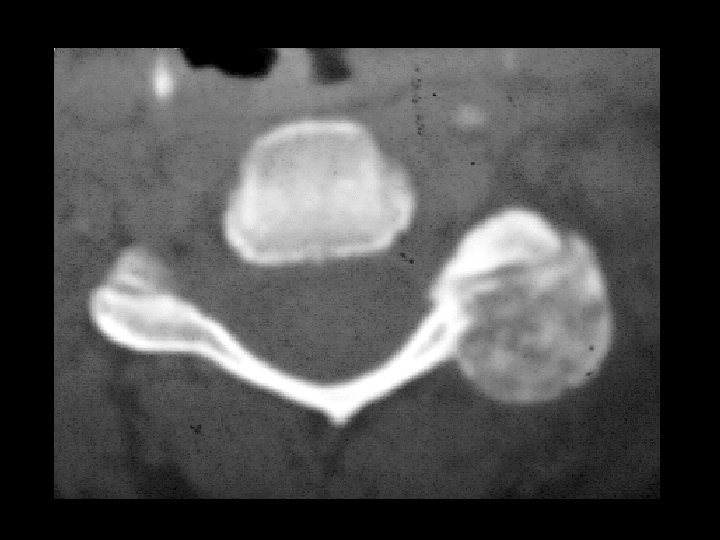

Osteoblastoma • Findings: – Very intense uptake in the posterior left cervical spine – CT scan is diagnositc • ddx: (intense uptake) – Osteiod osteoma – Fracture – Paget's disease – Metastasis – Osteosarcoma